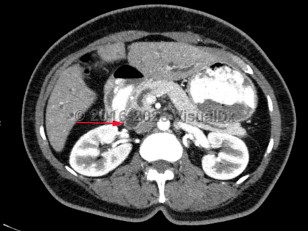

Carcinoma of the ampulla of Vater encompasses tumors that arise from within the ampullary complex (duodenal aspect of sphincter of Oddi, distal common bile duct [CBD], distal pancreatic duct, and papilla of Vater). These tumors often arise as part of a genetic syndrome, most commonly familial adenomatous polyposis (FAP) or hereditary nonpolyposis colorectal cancer (HNPCC), which tends to occur in a younger population. Patients with FAP require screening for duodenal adenomas including ampullary adenomas at the onset of colonic polyps or around age 25. Sporadic ampullary carcinomas typically occur around age 60-70.

Histologically, ampullary carcinomas can be divided into intestinal or pancreaticobiliary in origin. The intestinal type is more prevalent and is linked to mutations in KRAS and COX-2. Patients with intestinal-type ampullary carcinoma have a better prognosis. Painless jaundice (Courvoisier sign) is the most common clinical manifestation of ampullary carcinoma. This is caused by mechanical compression of the distal CBD by tumor. The remainder of patients can present with iron deficiency anemia or occult gastrointestinal tract bleeding. Silver stool may occur. More vague symptoms such as abdominal pain, nausea, fever, and dyspepsia can also occur.

The diagnosis is made with tissue biopsy. These tumors are staged using the T (tumor), N (lymph node), and M (metastasis) classification. Prognosis is dependent on tumor stage and histologic type. The 5-year survival for stage 1 disease is 84%; stage 2 is 70%; stage 3 is 27%; and stage 4 is 0%.